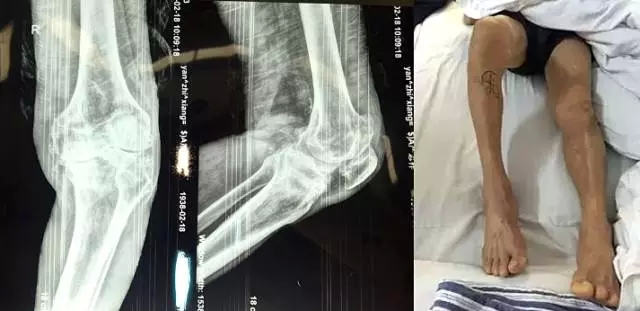

嚴(yán)老伯今年76歲,是勾山人。他右膝關(guān)節(jié)疼痛已有20多年。近五年來,嚴(yán)老伯右膝疼痛不斷加劇,右腿不僅不能自由行走,連彎曲也成了問題,最多只能彎曲50度左右。嚴(yán)老伯內(nèi)心郁悶,他說這腿把他折磨得非常痛苦,每天只能靠輪椅過日子,拖累了家人,心里十分歉疚。

“嚴(yán)老伯的右膝患有重度關(guān)節(jié)骨性關(guān)節(jié)炎,右膝內(nèi)翻畸形,如果再晚點(diǎn)來就醫(yī),他的狀況還會持續(xù)變壞。”危立軍替嚴(yán)老伯仔細(xì)檢查之后說,“鑒于他的情況,我們建議實(shí)行人工膝關(guān)節(jié)表面置換術(shù)。”

2月26日,嚴(yán)老伯在廣安醫(yī)院關(guān)節(jié)科做了膝關(guān)節(jié)表面置換手術(shù),從切開到縫合結(jié)束僅花了一個半小時。手術(shù)全過程病人基本上沒有手術(shù)后切口疼痛感,出血量不到150ml。術(shù)后第二天,他的右腿就能伸直了。

今天上午,主治醫(yī)生危立軍巡查病房時說:“嚴(yán)老伯的手術(shù)很成功,病人是非常嚴(yán)重的屈曲攣縮并內(nèi)翻畸形,膝關(guān)節(jié)平臺內(nèi)側(cè)骨缺損很嚴(yán)重。但我們采取了目前國際上最先進(jìn)的手術(shù)方法,無痛化病房管理和快速康復(fù)理念,所以病人恢復(fù)很快。”